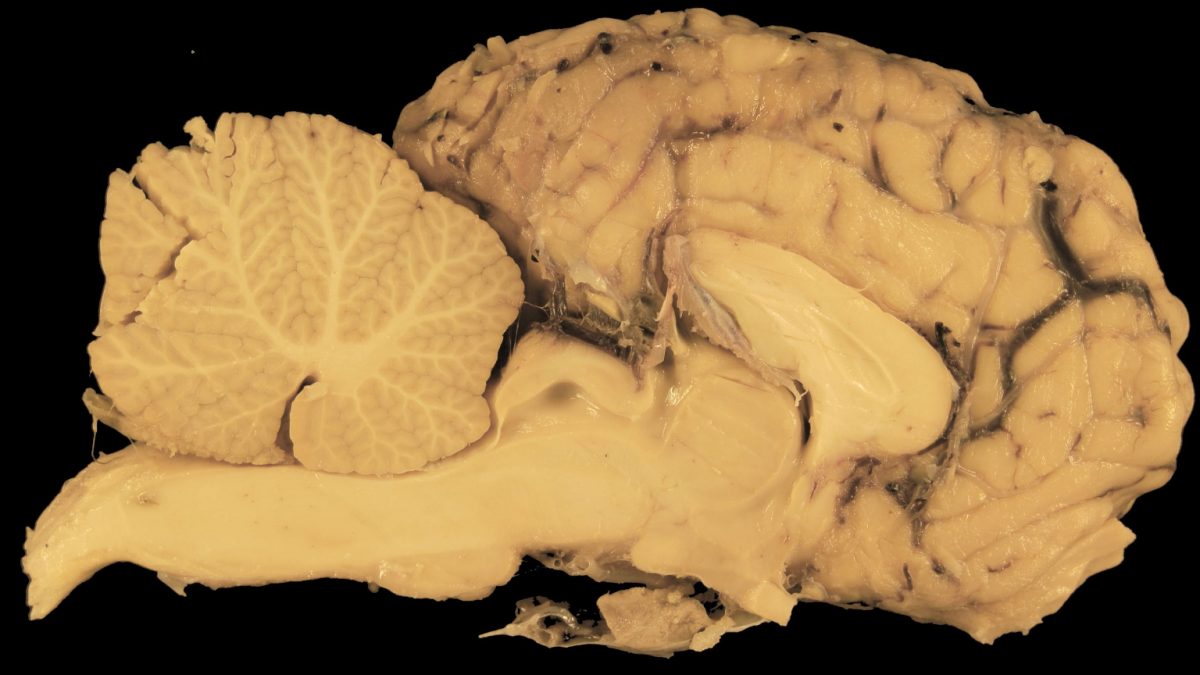

Az élő agy darabkái épp úgy néznek ki, mint bármely más szövetdarab - az idegszövet rózsaszínű, tömör apró hurkái. De más, - a kutatás céljára adományozott egyéb szövetekkel vagy szervekkel ellentétben, - ezek őrzik az ember emlékeit, gondolatait és érzéseit.

Az ilyen adományok elengedhetetlenek azokhoz a feltörekvő kutatásokhoz, amelyek célja annak megválaszolása, hogy mi tesz bennünket emberré. Például a Seattle-i Allen Agytudományi Intézet kutatói élő agyszövettel végeznek kísérleteket, hogy megértsék az emberi agy sejtjeinek működését. Ezeket az értékes mintákat, - amelyeket általában orvosi hulladékként dobnak ki, - agyműtéten átesett betegek adományozzák, és azonnal a laboratóriumba sietnek velük, amíg az idegsejtek még életképesek.